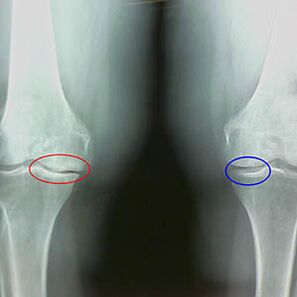

Zgodnje X -Ray značilnosti druge faze artrotroze kolena:

- Koničasti robovi med -odpisovalnih tuberklov na golenici, kjer je pritrjen križni ligament;

- zoženje vrzeli na medialni strani;

- Koničasti robovi kondilov kosti na medialnih straneh, manj pogosto v bočnih - odvisno od razvoja deformacije valgusa ali variornega sklepa.

Za drugo stopnjo v Larsenu Značilna vrzel za več kot 50% je značilna, vendar je to mogoče preveriti le v dinamiki ali v primerjavi z za razliko od sklepa.

Radiograf prikazuje prisotnost osteofitov, spremembo prostora med kosti stegnenice in golenice, kar kaže na izgubo hrustanca v kolenu. Včasih X -Rara kolenskih sklepov kaže na pomembne znake obrabe hrustanca, vendar pacienti ne doživljajo velike bolečine.Nasprotno, artroza prve stopnje lahko moti funkcijo kolena, ker so vzrok bolečine hipotonične mišice.